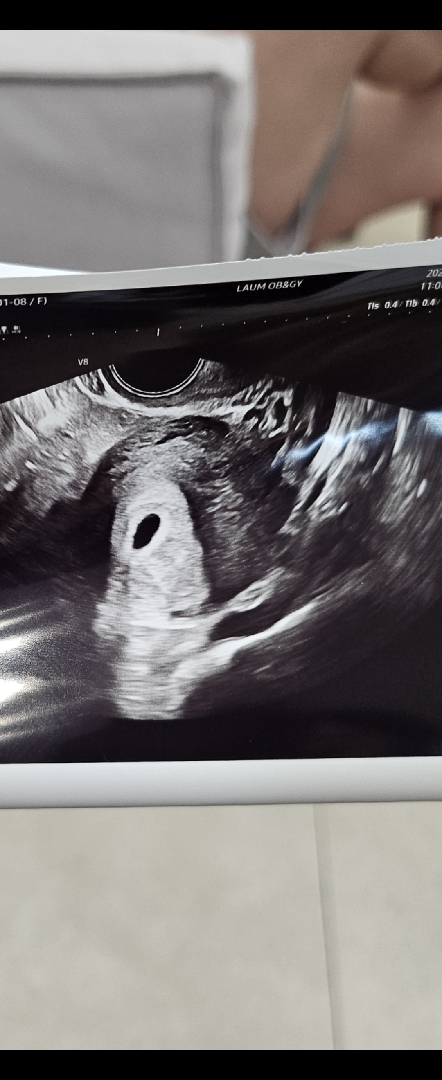

제가 첫 생리때부터 주기가 안맞기도 했고 성인되고 나서도 다낭성이 있어서 평소 생리주기 안맞았거든요..ㅠㅠ (2~3개월) 그래서 6/17 막생이였규... 7월도 생리를 안하거니 해서 넘어가고 있었는데 평소에 전혀 없던 생리통이 있는 것 같아서 임테기를 해보았더니 두줄떴어요 🤍 뜻밖의 자연임신..! 아마도 다낭성때뮨에 배란이 2-3주 지연된 것 같아요.. 지난주 월요일엔 처음갔던 병원에서 아직 너무 이르다고 3~4주 예상된다고 하셨는데 (아기집도 안보였음, 피검 수치 195) 일주일만에 간 다른 병원에선 아기집도 보이고 난황도 보였어요..! 이럴땐 아기집 크기로 주수 추정해본다규 하셨는뎅 갑자기 6주가 되어서 당황(?)스럽네요.. 전 5주 일 줄 알았는데 ㅠㅠㅠㅠ 이런분 계신가용.. 8/11(월) 임테기 두줄 8/19(화) 원포임테기 역전 2주후에 다시 오면 심장소리 들을 수 있을 것 같다고 하셔용 6주라고 하기엔 아기집이 넘 작은 것 같기두 하고.. 심장 소리도 듣는분들 많으시던데 ㅠㅠㅠㅠ 걱정되네요 🤣🤣